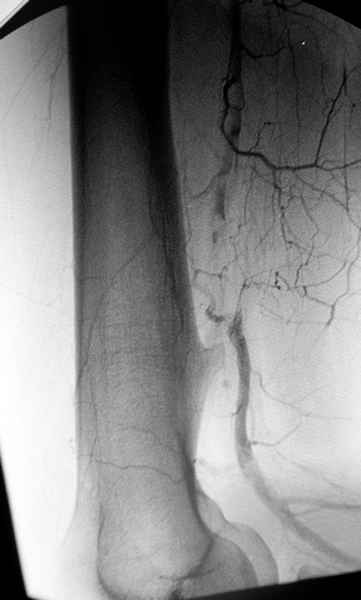

Ангиография подтвердила васкулярную аневризму в

результате давления экзостозом. Совместно с сосудистым хирургом была проведена плоскостная резекция с дальнейщим восстановлением сосуда венозным графтом.